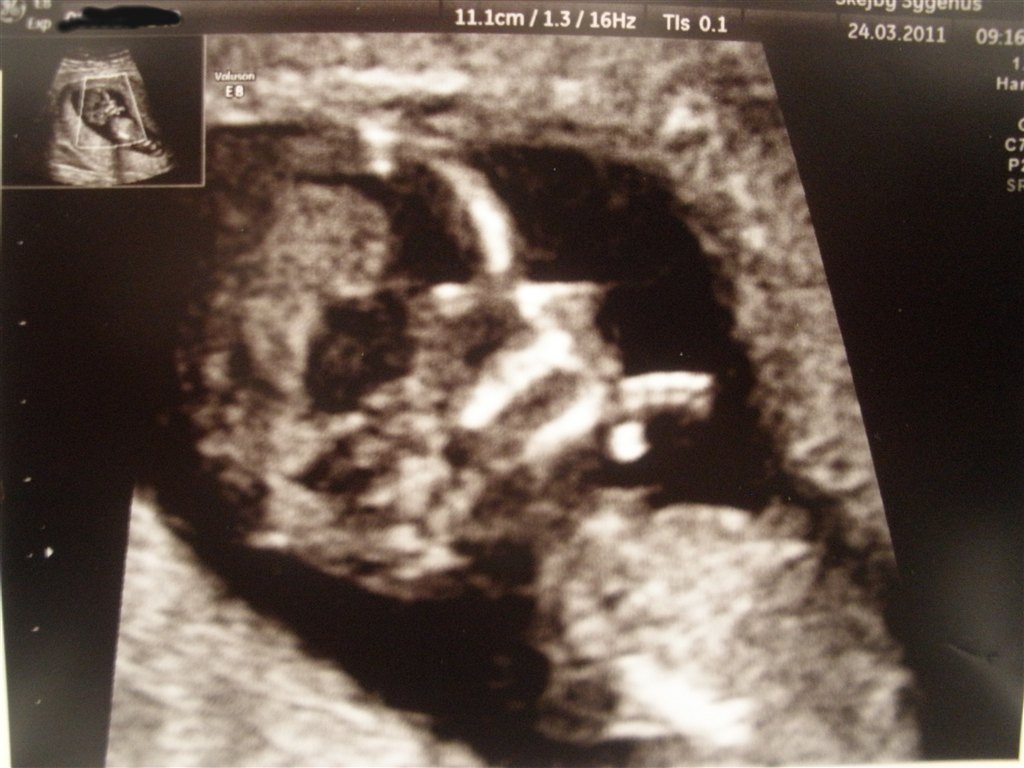

Glæd dig! Det er bare det største nogensinde!! Jeg var vist nok 12+4, og fik disse skønne billeder af prinsessen. Synes især det ene er FANTASTISK, det med hovedet bare. Fordi man kan se hendes hånd med alle 5 fingre knyttet sammen

Vedhæftede fotos (klik for at se i fuld størrelse)